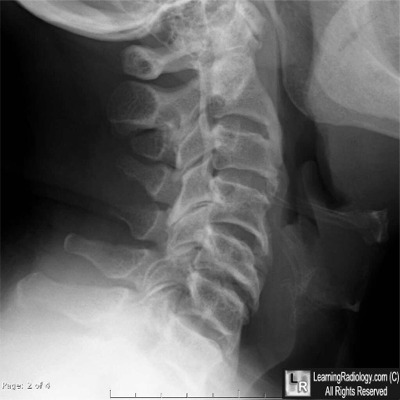

Lateral Cervical Spine Radiograph

What is the most likely diagnosis?

- 47 year-old male with numbness in arms

- Ankylosing Spondylitis

- Diffuse Idiopathic Skeletal Hyperostosis

- Rheumatoid Arthritis

- Hyperparathyroidism

- Ossification of the Posterior Longitudinal Ligament